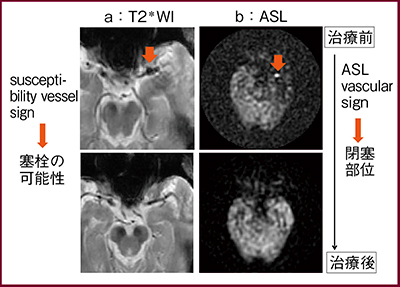

T2*強調画像では血栓部位の低信号(susceptibility vessel sign:図2a↓)が認められ塞栓の可能性が示唆されたが,ASLでは閉塞部位を示すvascular signの高信号(図2b↓)が認められた。また,虚血部位のT2*強調画像(図3)では虚血サイン(ischemic vessel sign)が認められ,ischemic penumbra(可逆的な前梗塞領域)の存在を示す所見である。

図2 治療前後のMR画像:血栓部位の診断